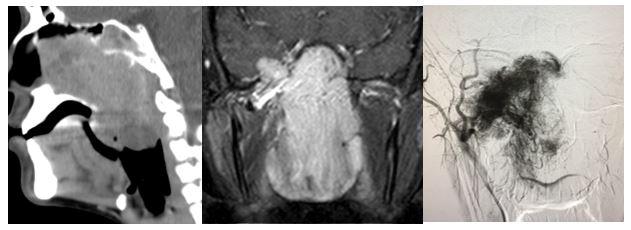

1. 04/2017. Masculino 9 años con obstrucción nasal de inicio gradual, epistaxis recurrente derecha, presentando masa en fosa nasal derecha de 3 años de evolución con extensión a seno maxilar, fosa pterigomaxilar e infratemporal derecha, así como Iisis de piso de orbita. Clasificación IIC (Radkowski) III (Chandler). Se realiza angiografía, embolización desde arteria carótida externa y se realiza resección vía Weber Ferguson, con resección completa del mismo, con buena evolución a 16 meses de posquirúrgico sin recurrencia.